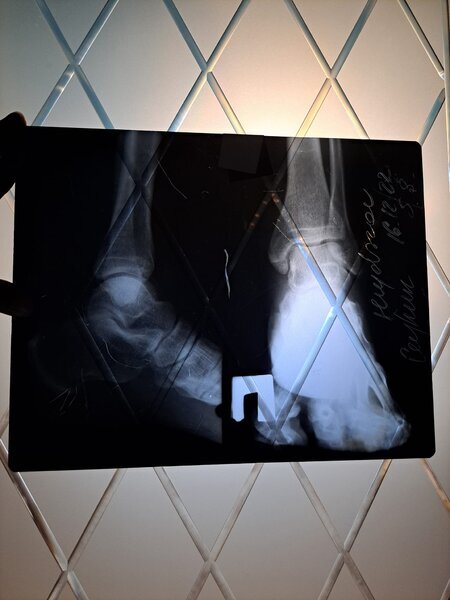

"Şikayətim Elmi-Tədqiqat Travmatologiya və Ortopediya İnstitutunda qeyri-rəsmi çalışan rezident Ağa Mirməhəmməd Mirhaşım oğlundandır. Həyat yoldaşım Ceyhun Heydərov avtomobil qəzası keçirdiyi gün Travmatologiya İnstitutuna müraciət etmişdir. İlkin baxış və rentgen müayinələrindən sonra özünü həkim kimi təqdim edən Ağa Mirməhəmməd rentgen nəticələrini düzgün oxuya bilməmiş və yoldaşımı arxayın edərək heç bir sınıq olmadığını, əzilmə və sıyrıq olduğunu demiş, xəstəni evə yola salmışdır.

Bir neçə gün sonra ayağın göyərdiyini və şişdiyini gördüyümüz üçün yenidən Travmatologiya İnstitutuna müraciət etmişik. Bu dəfə bir digər həkim travmatoloq 16.12.2022-ci ildə çəkilmiş elə həmin rentgen nəticələrinə baxaraq ayağın topuq nahiyəsində sınıq olduğunu aşkar etmiş. Təkrar KT müayinəsi etdirmiş və sınıq olduğunu tam dəqiqliklə təsdiqləmişdir. (Eyni zamanda tam əmin olmaq üçün özəl klinikalardan birinə də müraciət etmişik)

Sınıq ilk gün Ağa Mirməhəmməd tərəfindən aşkarlanmadığı və dəqiq diaqnoz qoyulmadığı üçün sınıq yerdəyişmiş və nəticədə yoldaşım Ceyhun Heydərov 30.12.2022-ci ildə əməliyyat keçirmişdir".